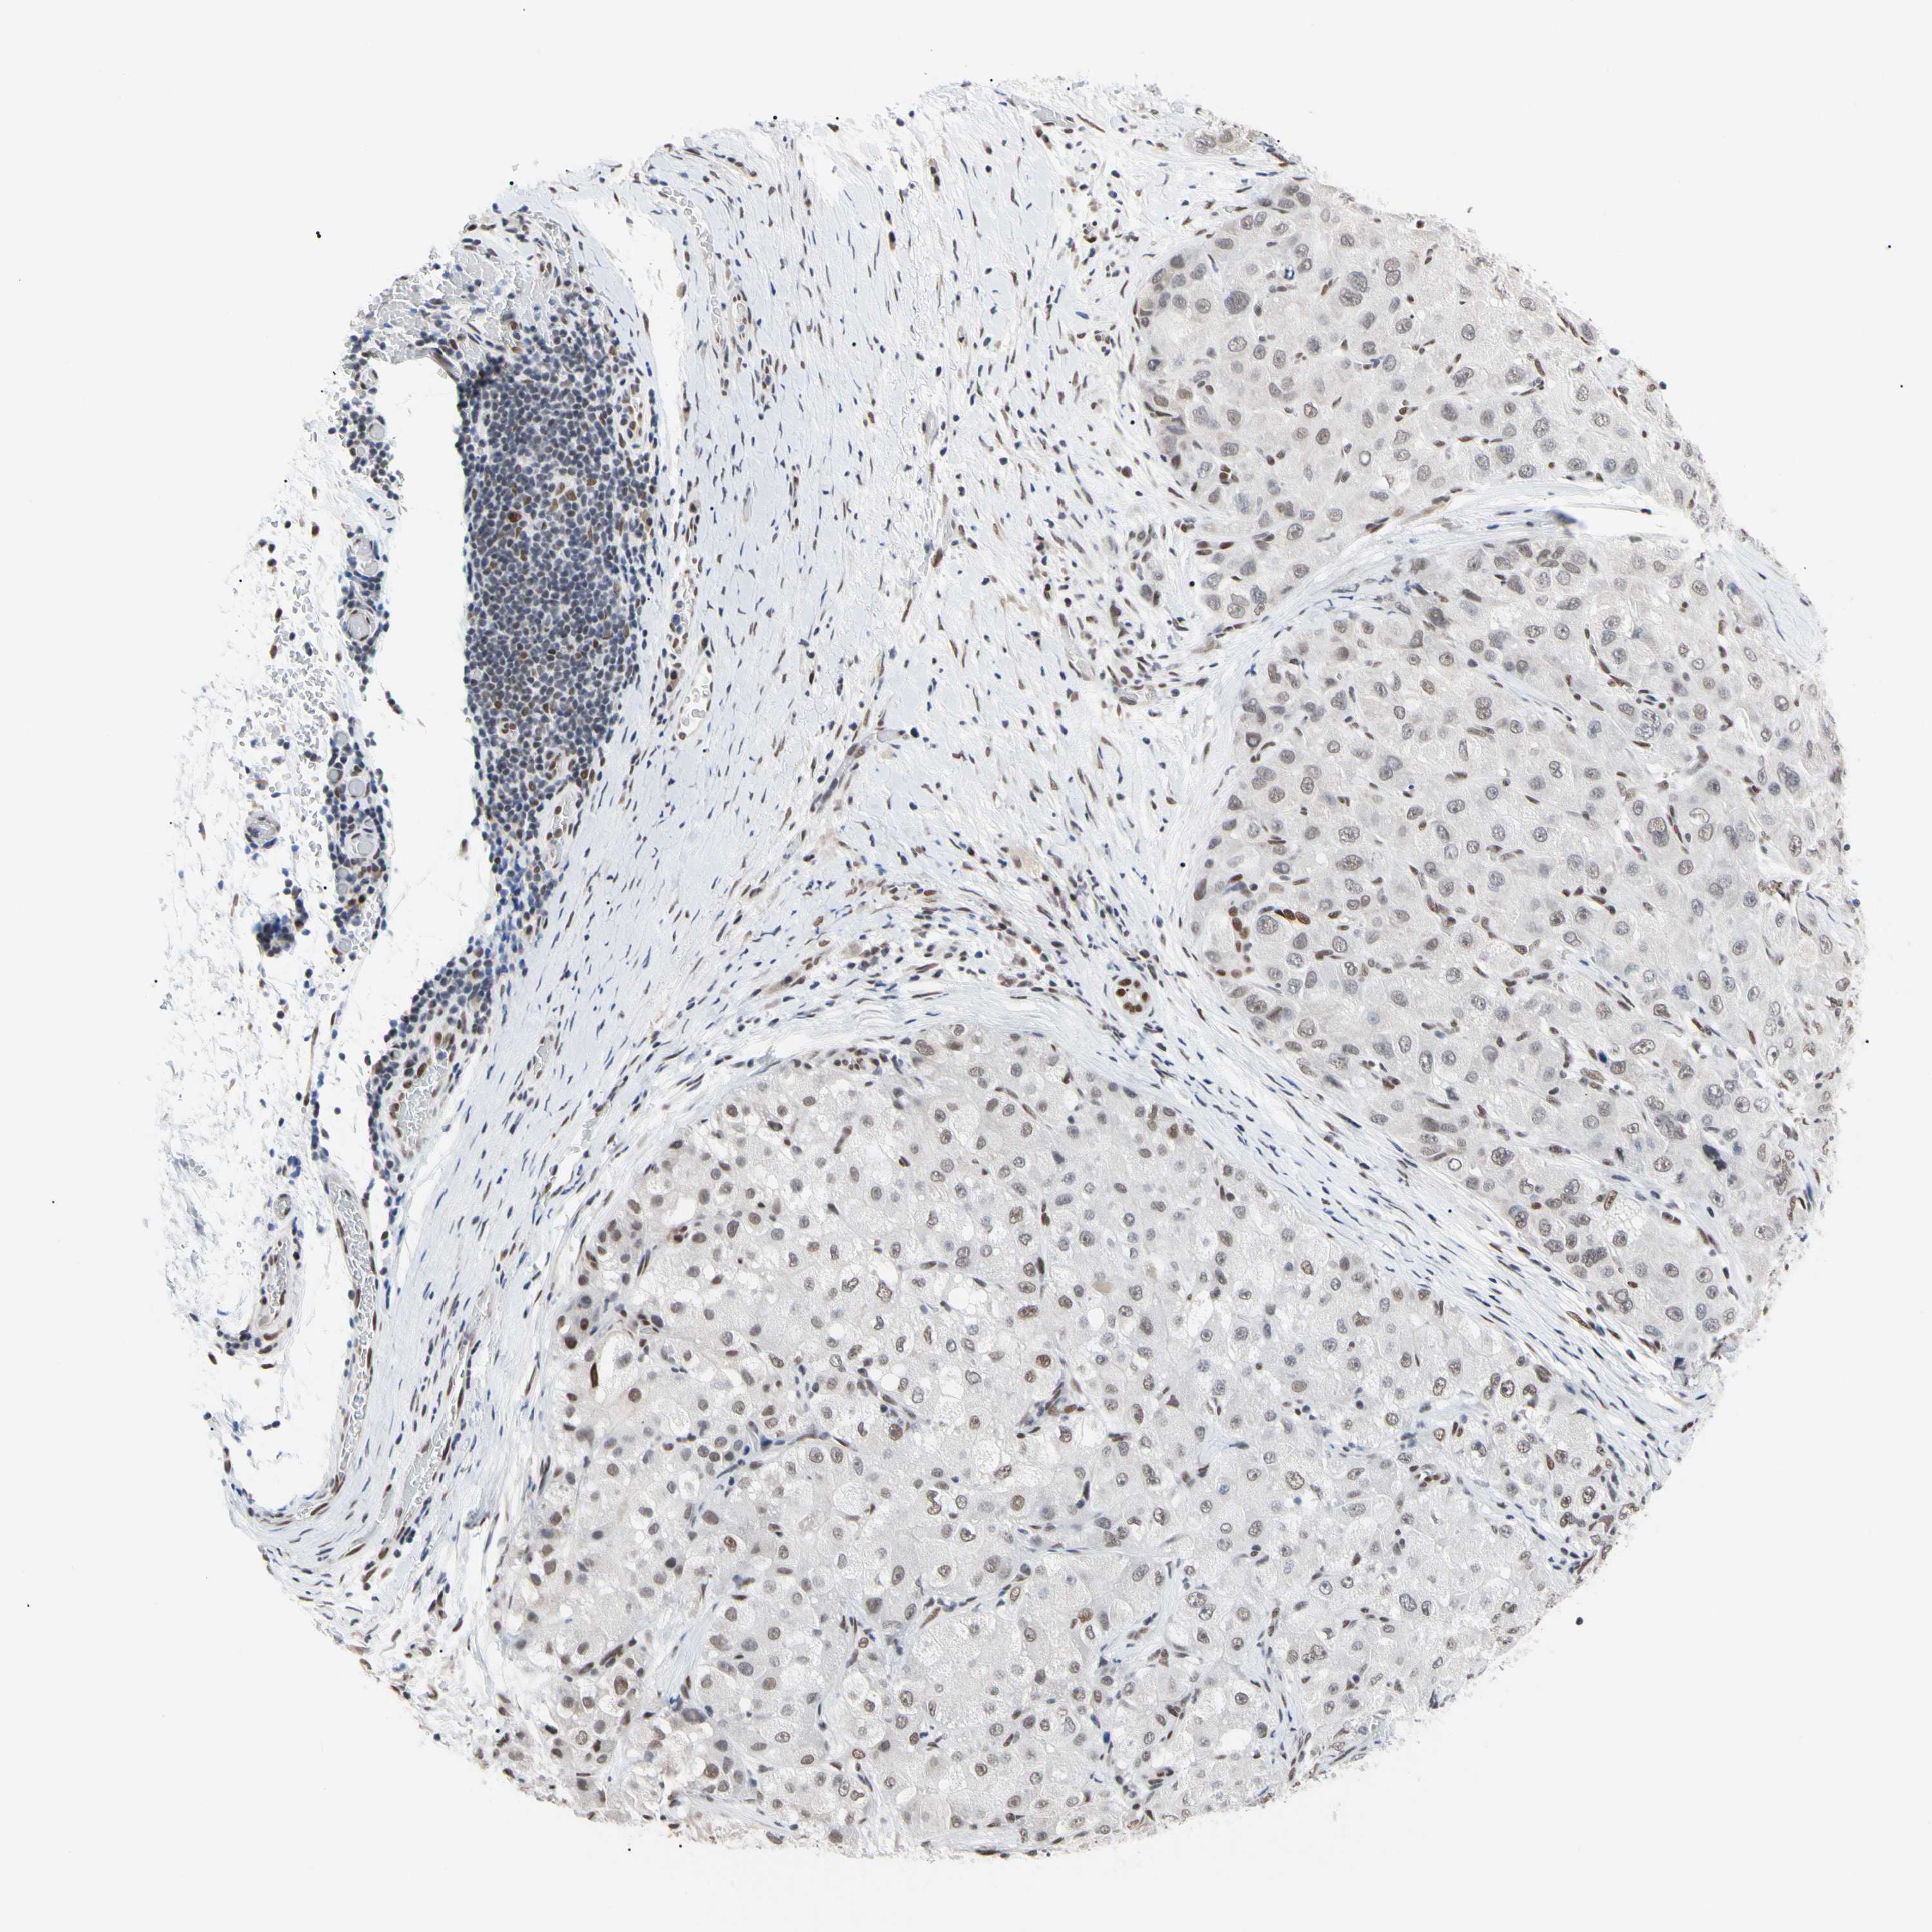

LIVER CANCER - Protein expressioni

A mouse-over function shows sample information and annotation data. Click on an image to view it in a full screen mode. Samples can be filtered based on level of antibody staining by selecting one or several of the following categories: high, medium, low and not detected. The assay and annotation is described here.

Note that samples used for immunohistochemistry by the Human Protein Atlas do not correspond to samples in the TCGA dataset.

Antibody stainingi

Antibody staining in the annotated cell types in the current human tissue is reported as not detected, low, medium, or high, based on conventional immunohistochemistry profiling in selected tissues. This score is based on the combination of the staining intensity and fraction of stained cells.

Each image is clickable and will lead to virtual microscopy that enables deeper exploration of all samples and also displays staining intensity scores, fraction scores and subcellular localization as well as patient and tissue information for each sample.

Antibody HPA008320

Antibody HPA008502

Staining

High

Medium

Low

Not detected

Intensity

Strong

Moderate

Weak

Negative

Quantity

>75%

75%-25%

<25%

None

Location

Nuclear

Cytoplasmic/membranous

Cytoplasmic/membranous,nuclear

Cholangiocarcinoma

Carcinoma, Hepatocellular, NOS